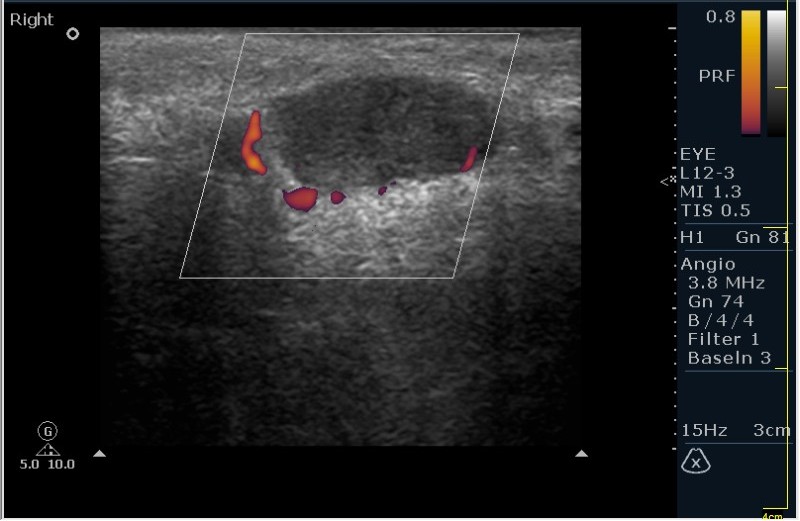

Мужчина 68 лет, направлен на УЗИ правой слюнной железы. Жалобы на пальпируемое, малоболезненное плотное образование за правым ухом.

Солидное!!!! Я тоже ТАБ хотел сделать, но ЛОР заказал КТ... А какие мысли будут?

Первая мысль о очаговом воспалении, деструктивной фазе, но нет клиники.

Тумор?

Клиники нет, тумор на первом месте. В принципе КТ (или МРТ) заказывают для диффиренцировки зло/добро. Плюс посмотреть есть ли локальное растпространение. Но в данном случае я думаю УЗИ с ТАБ было бы достаточно.